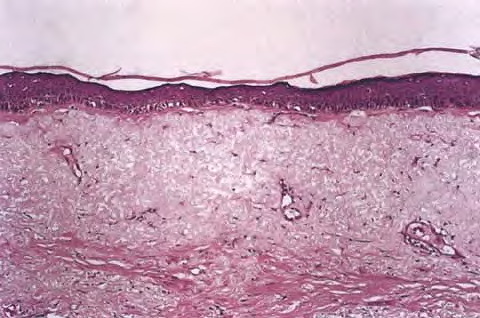

Read MoreAged skin = شيخوخة الجلد Aging of Skin ▪ EFFECTS OF AGING In both developed and developing nations, the number and proportion of older people are increasing. Thirty-one percent of the U.S. population is expected to be 55 years of age or older by the year 2030.1 This demographic shift compels health care […]